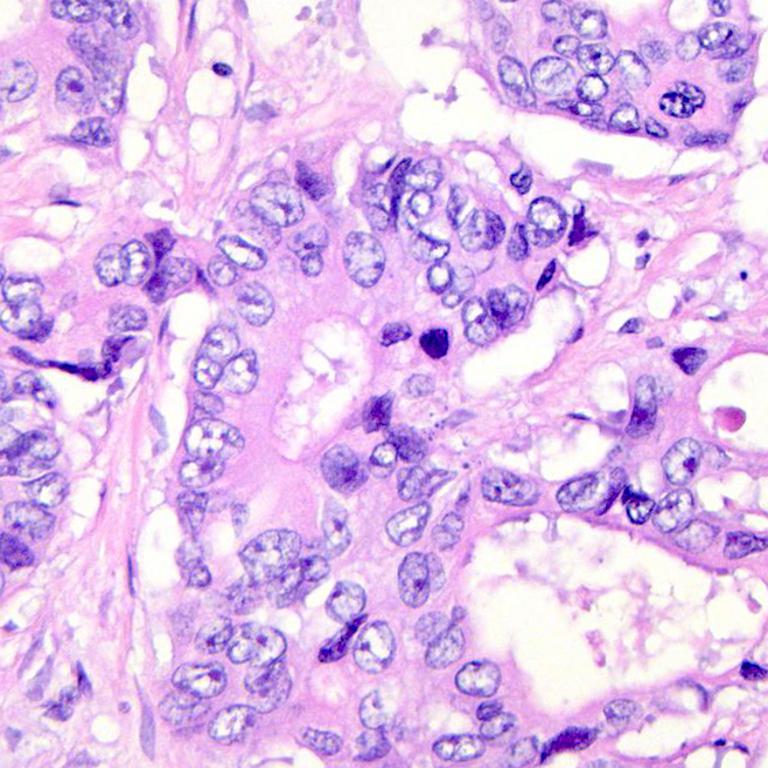

We consider two binary histopathology classification tasks, both framed as “cancer” vs. “non cancer”. The first dataset is the Ovarian Cancer & Subtypes Histopathology dataset111https://www.kaggle.com/datasets/bitsnpieces/ovarian-cancer-and-subtypes-dataset-histopathology, which contains digital pathology patches extracted from hematoxylin and eosin (H&E) stained ovarian tissue slides. We group the available subtypes into a single positive class (ovarian cancer) and use benign or non tumoral tissue as the negative class.

The second dataset is a subset of the LC25000 dataset222https://www.kaggle.com/andrewmvd/lung-and-colon-cancer-histopathological-images, which contains colon histopathology images with normal and tumoral samples. We select only colon images and map them to a binary label (cancer vs. non cancer). Representative examples of ovarian and colon patches for both classes (Figure 2).

| (a) Ovarian cancer | ||

| (b) Ovarian normal | ||

| (c) Colon cancer | ||

| (d) Colon normal | ||